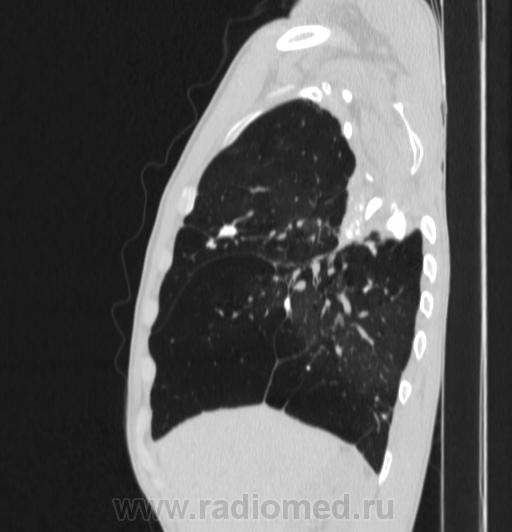

Состояние после торакопластики.

Молодой человек 30 лет, в 04 году выявлен фиброзно-кавернозный ТБ, в течение 12 месяцев лечился в стационаре, прооперирован-5реберная торакопластика справа, через 3 года переведен в 3ГДУ, в 10году снят с ДУ по излечению. Пришел провериться по ухудшению состояния. На КТ легких данных за рецидив ТБ, вроде нет. С " торакопластикой" был единственным пациентом на учете.

Состояние после правосторонней 5-реберной торакопластики по поводу ФКТ.Грубые остаточные изменения:поликистоз,буллезно-дистрофические изменения,плевропневмоцирроз правого легкого..Нет ли  мелкоочаговой диссеминации в обоих легких?Нужен Rархив.(ПТД).

Нет, это кальцинаты и более плотные уже. Архив только пленочный, 8 лет назад "цифры" не было. Можно и пленку перефотать...

Редко встречалось, а на КТ вижу впервые, спасибо за случай! На показанных изображениях отсевов не увидела.